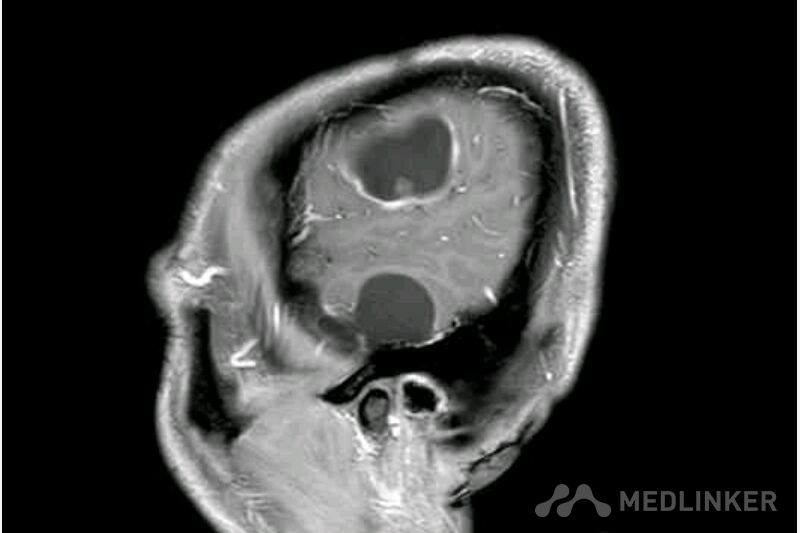

脑囊虫病高清影像资料分享

脑囊虫病经典资料